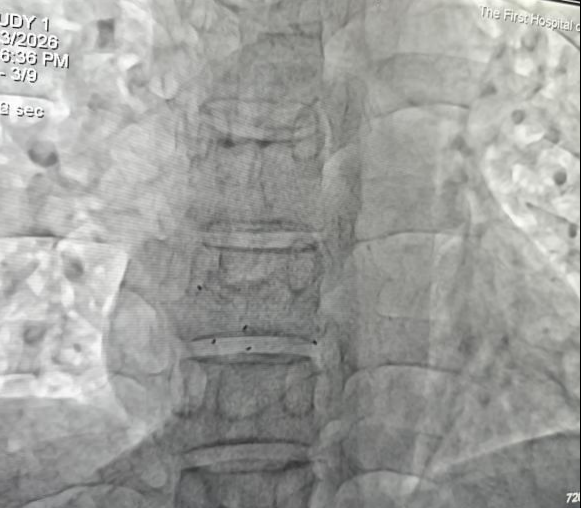

手术当日,心血管内科团队提前制订周密介入方案。术中,团队经股静脉穿刺建立通路,将输送鞘管送达心脏房间隔缺损部位,精准释放可降解封堵器,整个操作在X线透视和超声心动图的引导下完成。患者全程无明显痛感,术后次日即下床活动。

术后超声X线透视影像